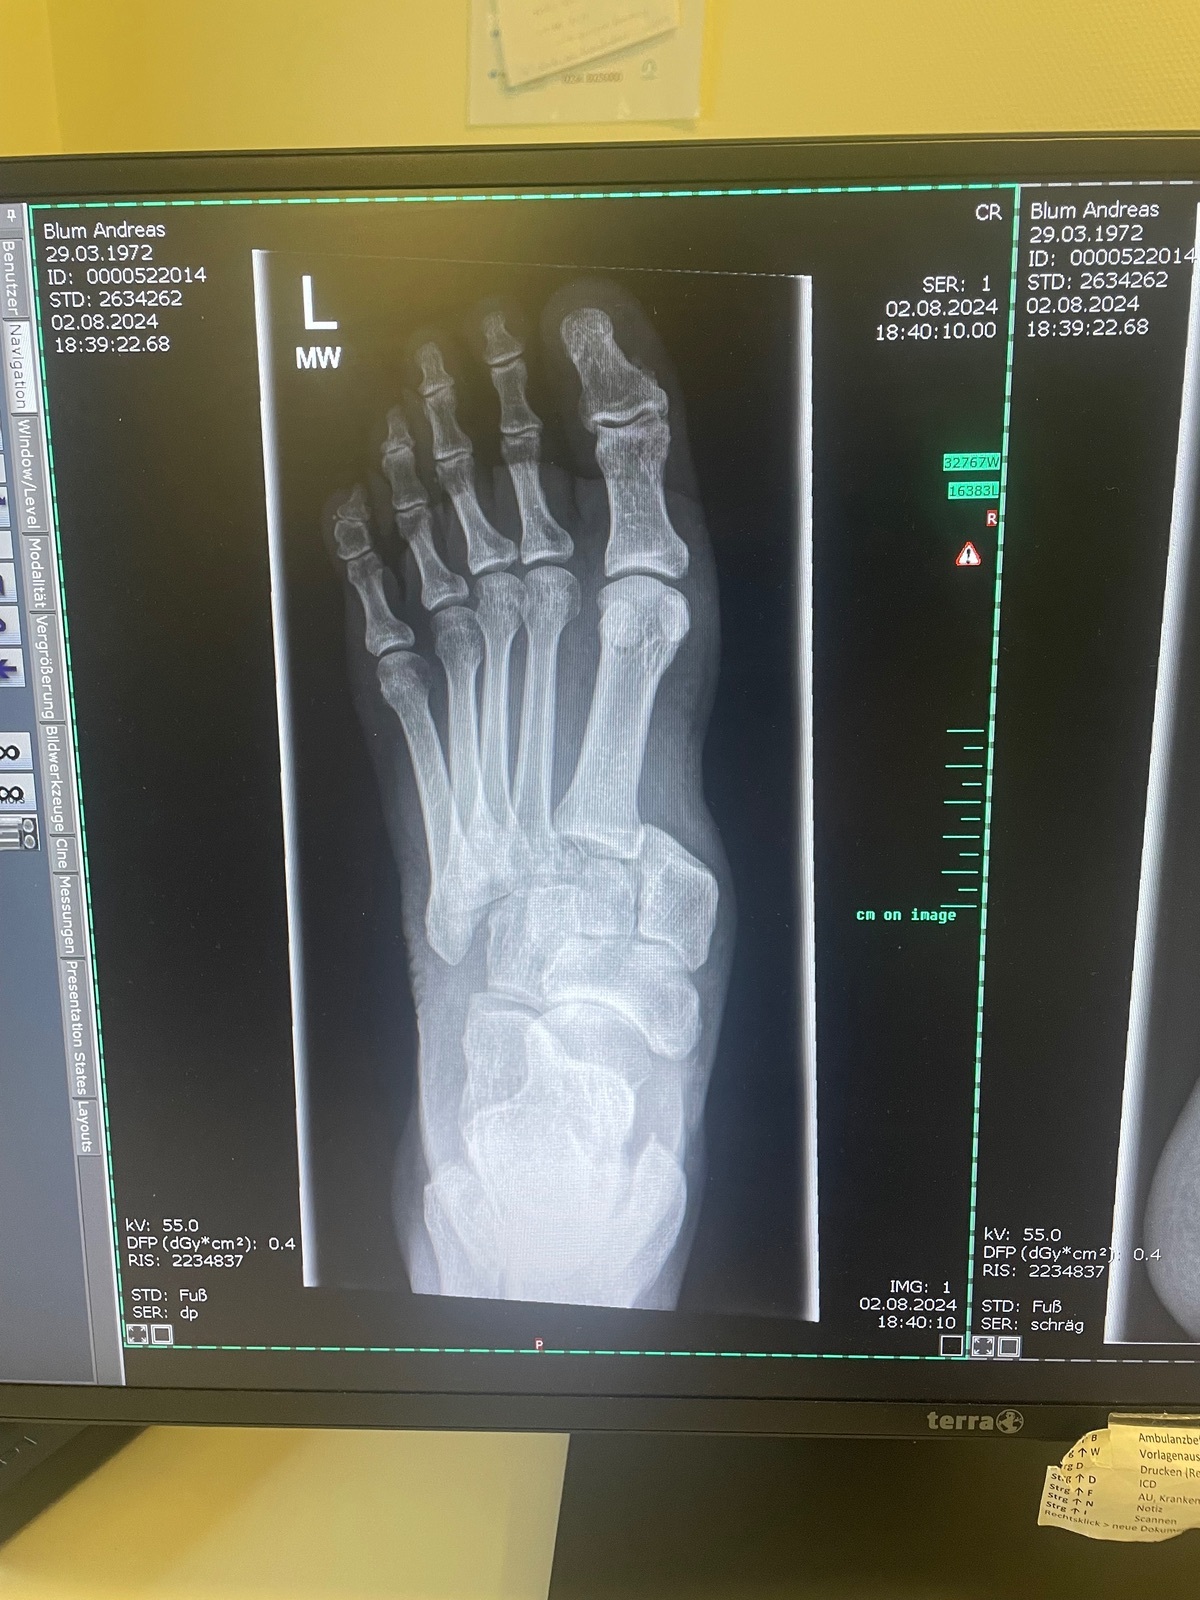

Offensichtlich traf meine Fußraste oder ein anderes hervorstehendes Teil meinen Vorderfuß und klemmte den ein. Die Folge: alle Mittelfußknochen wurden aus der Position gedrückt und etwa „eine Zehe“ weiter nach links verschoben.

Die Sache nimmt mich für diese Saison aus dem Rennen und wird mich sicher 4-5 Monate beschäftigen, drei davon, ohne dass ich den Fuß belasten darf, anschließend Physio.